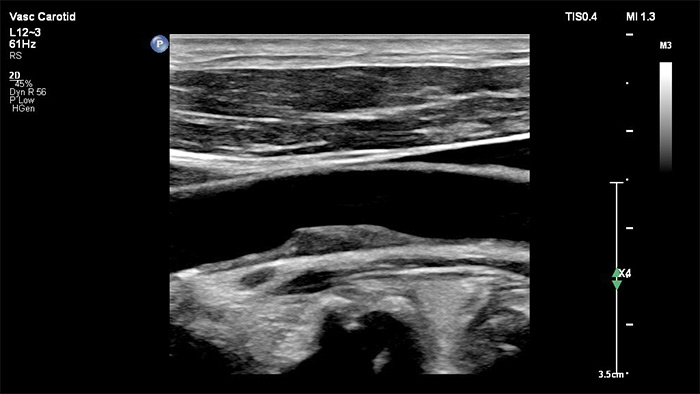

In der Bildverarbeitung der jüngsten Generation von Philips wird die Gefäßdiagnostik durch die exzellente Abgrenzung der Gefäße und genaue Erkennbarkeit der Plaque-Beschaffenheit, auf eine neue Ebene gehoben. Auch bei technisch schwierigen Gefäßuntersuchungen erhöht XRES Pro die Diagnosesicherheit durch die Reduktion von Schleiern und Artefakten.